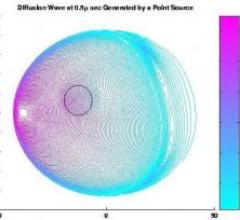

October 7, 2009 - Mathematical solutions to enhance the image quality of diffuse optical tomography (DOT) to use for breast cancer screening is in development at Clemson University in collaboration with researchers at the University of Bremen, Germany.